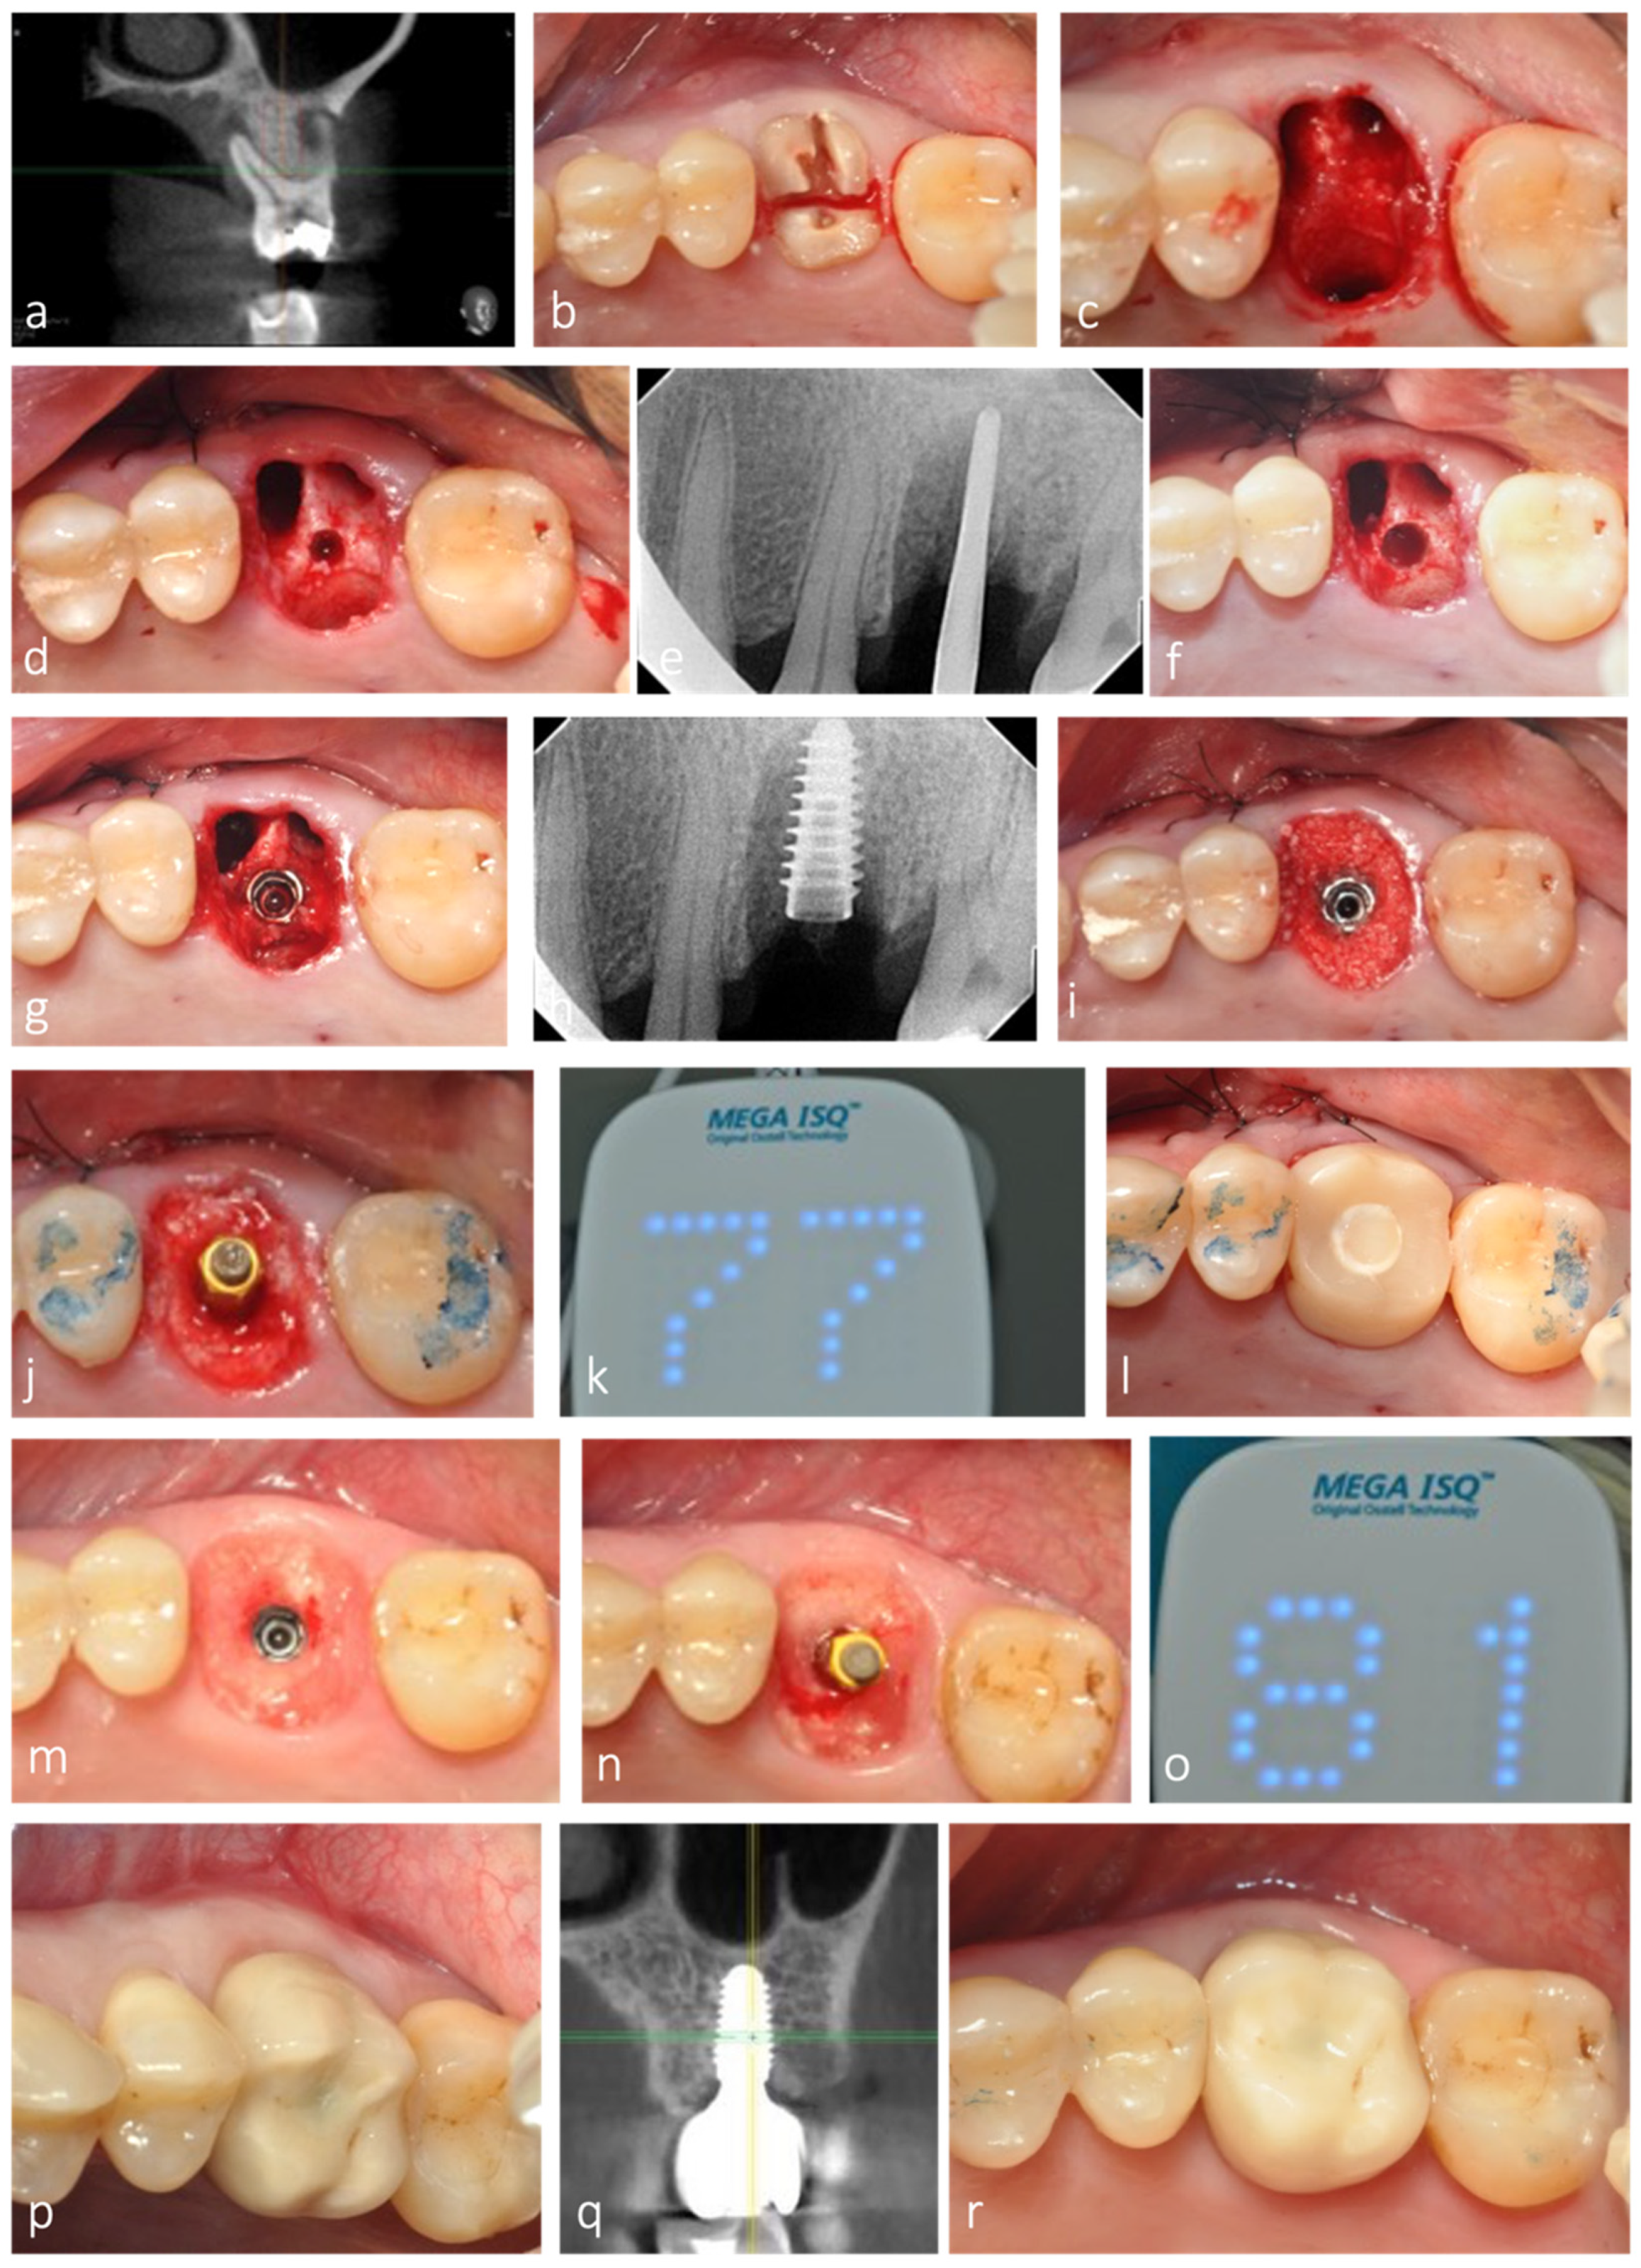

All sockets evaluated in this retrospective analysis were grafted with either allograft or alloplast (Novabone®). Bone grafting of the remaining socket voids adjacent to an immediate implant is not essential for osseointegration to occur, especially if the outer walls of the socket are intact [,,]. However, its combination with a customized healing abutment, acting as a prosthetic socket seal device minimizes the amount of ridge contour change after tooth extraction and IIP, thereby contributing to better esthetics and restorative contour [,], as observed in this study (Figure 8).

Figure 8.

Representative clinical case with 3-year clinical and radiographic follow-up. (a) CBCT of maxillary left first molar showing periapical infection with extensive bone loss buccally and palatally. (b) Root section for tooth extraction as atraumatic as possible. (c) Septum preservation after extraction. (d,e) Initial osteotomy depth at 10 mm. (f) Implant site preparation, optimized with osseodensification. (g,h) Implant placed in the expanded septum. (i) Allograft placed in the root sockets to fill the extraction socket. (j–l) Adequate implant stability allowed for the placement of a fully contoured customized socket sealing healing abutment out of occlusion. (m) Healing after 3 months, with contour maintenance. (n,o) ISQ measurement after osseointegration period. (p–r) Clinical and radiographic follow-up after 3 years.